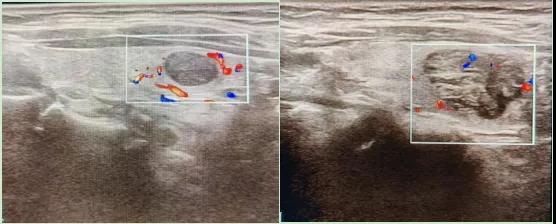

彩色血流顯示:用紅藍(lán)色標(biāo)記血流信號,區(qū)分腫瘤的供血情況。

1.形態(tài):良性多呈圓形,邊界清晰;惡性可能不規(guī)則、邊緣模糊。

2.回聲:低回聲結(jié)節(jié)風(fēng)險(xiǎn)較高(像“烏云”一樣暗)。

3.鈣化:細(xì)小砂礫樣鈣化提示惡性可能。

4.血流信號:惡性結(jié)節(jié)常有豐富紊亂的血流。